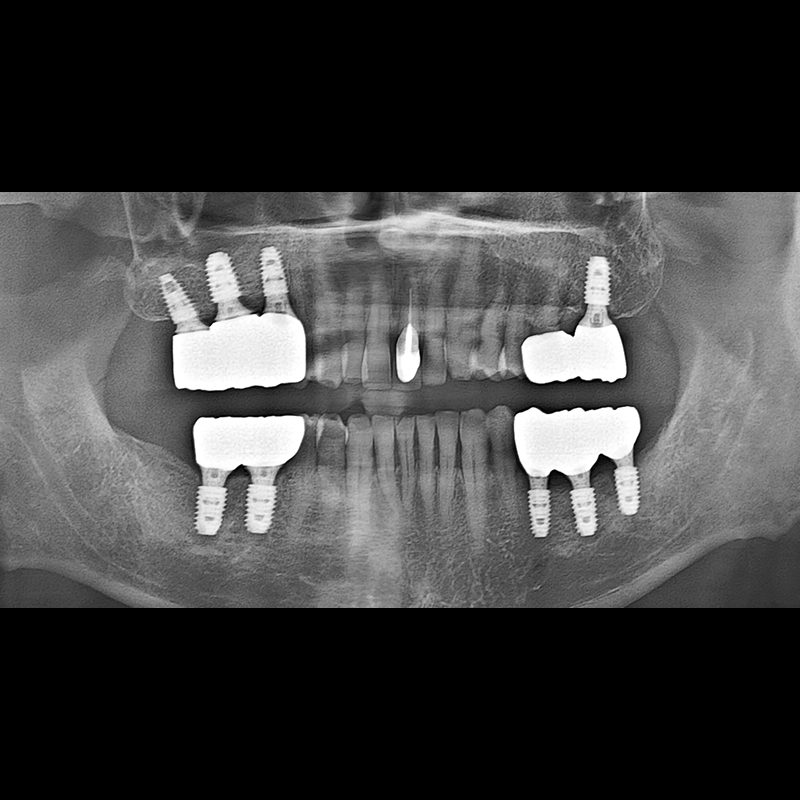

BEFORE AFTER

Implant before and after 2025.05.30

Implants were placed in the missing tooth and in the tooth position where it was difficult to save.